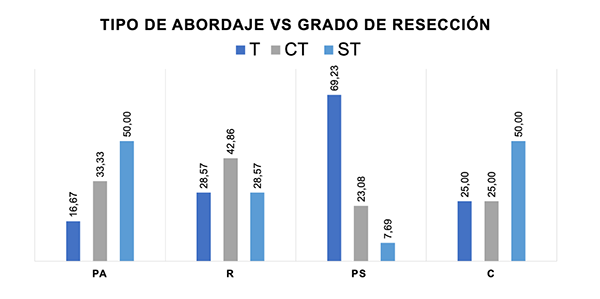

Figura 1. Tipos de abordajes vs grado de resección. Se muestra en el grafico el porcentaje de pacientes que en cada tipo de abordaje se les realizo una resección total (T), casi total (CT) o subtotal (ST).

Abordaje Retrosignoideo: Pese a las constantes publicaciones que implican un cambio en la filosofía del manejo de este tipo de tumores, el abordaje retrosigmoideo sigue siendo el caballo de batalla de la mayoría de los neurocirujanos debido a su facilidad, versatilidad y capacidad de exposición de las estructuras neurovasculares contenidas en el ángulo pontocerebeloso. Un estudio reciente menciona la importancia de esta vía en el manejo de los MRPC, mostrando una resección extensa en gran parte de los pacientes y una evolución favorable en el caso de una resección subtotal combinada con radiocirugía.17 Este fue el abordaje quirúrgico más utilizado en nuestra serie; fue utilizado en el 44% de los casos, logrando una resección adecuada en el 71,43% de los pacientes intervenidos (Figura 1). Creemos que este abordaje es el ideal para los tumores con un crecimiento hacia el clivus inferior, que presentan una extensión lateral al CAI y/o que han desplazado posterolateralmente el pedúnculo cerebeloso medio.18

Abordaje Transpetroso Anterior : Este abordaje implica el fresado extradural del apex petroso, y es la primera elección a nuestro entender, para tumores de pequeño o mediano tamaño, que nacen en el sector petroso anterior y que se extienden hacia la fosa media; es importante que la lesión no se extienda por abajo del nivel del CAI.19,20,21 Desde un punto de vista quirúrgico este abordaje limita la visualización de tumores por debajo del clivus medio; sin embargo permite un adecuado acceso hasta la línea media clival. Además, es el único abordaje que ofrece una liberación de 360 grados del nervio trigémino. En nuestro estudio, representó el 20% de los abordajes realizados, y fue escogido en general cuando las lesiones comprometían el clivus superior y/o medio con extensión hacia la fosa media. Se consiguió una resección superior al 95% en la mitad de los casos (Figura 1).

Abordaje Presigmoideo: Ofrece una visión lateral de las lesiones con implantación en el clivus superior y medio. Este abordaje puede recibir distintas denominaciones siendo algo confuso en la literatura; también se lo conoce como abordaje transpetroso posterior. Sus variaciones dependen del grado de fresado de las estructuras óticas circunscritas al interior del hueso petroso y que deben ser preservadas o no de acuerdo al estatus neurológico preoperatorio; es dividido en 3 variantes: retrolaberíntica, translaberíntica y transcoclear.19,22,23,24 La variante retrolaberíntica implica un menor grado de fresado y pretende preservar la funcionalidad del nervio coclear.20 Si un paciente tiene poca o ninguna audición, es preferible la utilización de la variante translaberíntica; el fresado de los canales semicirculares en este abordaje permite mayor visualización y una mejor ventana de trabajo.24 En la presente serie, el 23,3% de los casos fueron realizados por esta vía; en todos los casos fue agregado como accesorio un abordaje subtemporal, con el objeto de ligar y cortar el seno petroso superior y luego seccionar el tentorio. La gran ventaja de esta vía es precisamente la sección del tentorio, que permite al cirujano tener un mayor y mejor ángulo de ataque del tumor; además, al utilizar el acceso subtemporal, permite la resección del tumor que se ubica por arriba del nivel del tentorio. Más del 70% de los pacientes en los que fue realizado el abordaje se consiguió una resección superior al 95% (Figura 7). La elaboración de este abordaje requiere de un entrenamiento microquirúrgico exigente que permita identificar y preservar las estructuras neurológicas a su paso.

Abordaje Combinado: Una acceso combinado, en nuestro estudio, fue definido como la utilización de más de una vía de abordaje (ejemplo: vía presigmoidea más vía retrosigmoidea; vía transpetrosa anterior más vía presigmoidea). La elección de la ruta quirúrgica transpetrosa combinada (transpetroso anterior más presigmoideo) es probablemente la combinación más utilizada. No obstante su utilización es controvertida, teniendo en cuenta que su elaboración implica un extenso fresado del hueso temporal, algunos autores sugieren que es la mejor elección para los MRPC de mediano o gran tamaño con extenso compromiso neurovascular pero con preservación de la audición.25 Al-Mefty et al1 informaron en su serie de 64 pacientes que la utilización de esta vía permitió una mejoría en la morbimortalidad y en la conservación de los NCVII y NCVIII. En el 13,3% de los casos fue necesario utilizar la combinación de varios abordajes (Figura 7).